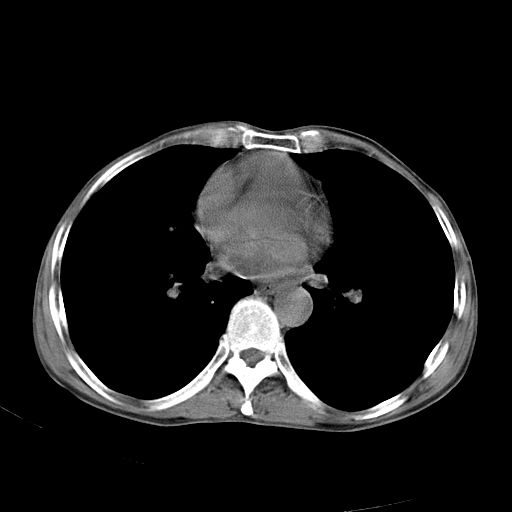

以下是引用zhangzhongshou在2007-5-24 12:55:00的发言:[br]1、右肺中叶中心型肺癌并右肺门、隆突下、纵隔淋巴结转移。右肺中叶阻塞性肺炎。

以下是引用苯小孩在2007-5-24 12:47:00的发言:[br]右侧肺门处不均匀密度软组织块影,远端肺组织见斑片模糊影,纵隔内淋巴结明显肿大,边界不清.<纵隔窗第12层面支气管内似见软组织结节>[br]考虑:1、右侧中央性肺癌并阻塞性肺炎并纵隔淋巴结转移可能性大.建议强化或纤支镜进一步检查.[br]2、隆突下淋巴结肿大/食道病变?请做鉴别检查.

以下是引用jw-830在2007-5-24 15:24:00的发言:[br][br] [br] 考虑右肺中央型肺癌并阻塞性炎症,右肺门及纵隔淋巴结转移。 [br] [br][br]